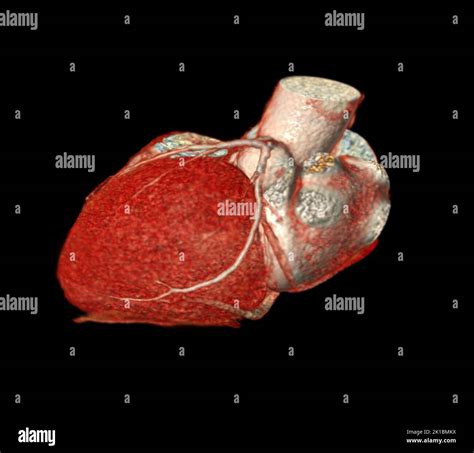

When it comes to diagnosing heart conditions, precision is paramount. A Cardiac CT, also known as a coronary computed tomography angiography (CCTA), has revolutionized the way medical professionals visualize the complex structures of the heart. By utilizing advanced X-ray technology coupled with powerful computers, this non-invasive diagnostic tool creates detailed, three-dimensional images of your heart, its arteries, and the surrounding tissues. Whether you are experiencing unexplained chest pain or have known risk factors for cardiovascular disease, understanding how this procedure works can help alleviate anxiety and prepare you for your medical journey.

At its core, a Cardiac CT scan is an imaging test that allows cardiologists and radiologists to see if your coronary arteries are narrowed or blocked by plaque buildup—a condition known as atherosclerosis. Unlike traditional stress tests, which provide functional information about how your heart handles exertion, a cardiac CT provides anatomical information. It captures images of the heart while it is beating, using sophisticated gating technology to synchronize the image acquisition with your heart rhythm.